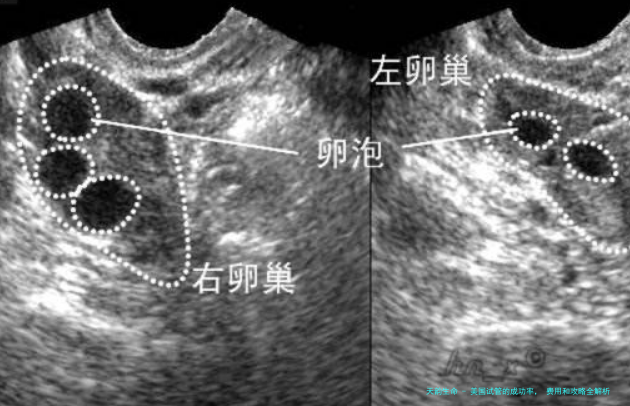

卵巢储藏:卵巢储备是指女性体内余下卵子的数量。卵巢储备量越大,试管婴儿成功率越高。